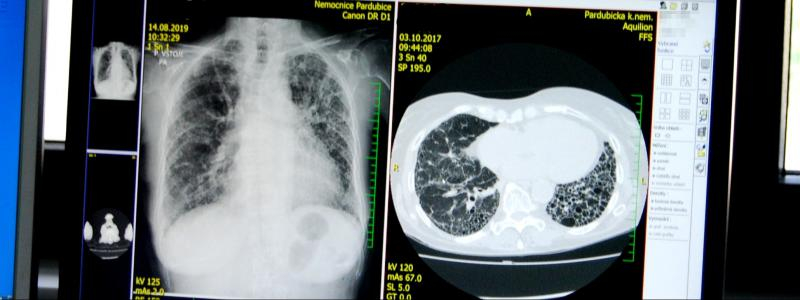

Idiopatická plicní fibróza je onemocnění, při kterém jsou vzdušné plicní sklípky nahrazovány hutnou fibrózní tkání, což vede k omezení funkce plic. Nemoc se projevuje nespecifickými příznaky, jako je kašel, obtížné dýchání, rychlá unavitelnost, hubnutí. Mohou být přítomny tzv. paličkovité prsty. Lékař při fyzikálním vyšetření většinou zjistí specifický poslechový nález (krepitus). V posledních několika letech jsou v naší republice k dispozici léky, které mohou zčásti ovlivnit nepříznivý průběh onemocnění, důležité je však včasné rozpoznání nemoci.